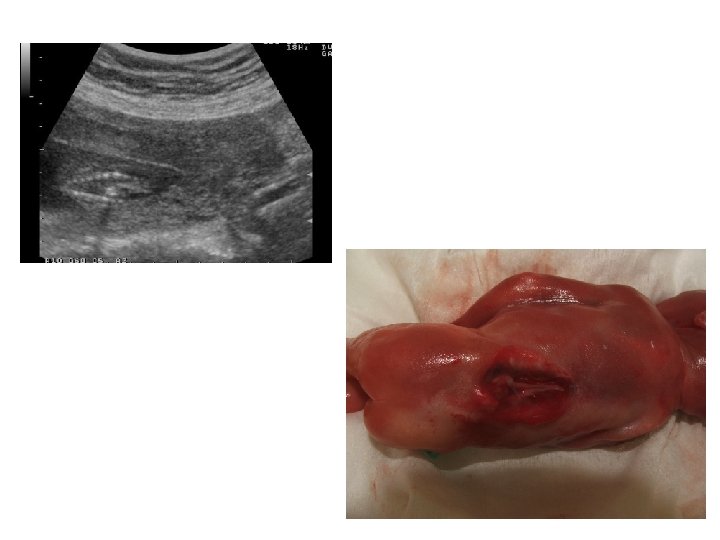

Échographie précoce du 1 er trimestre Indications : – si la grossesse est associée à des symptômes inhabituels (métrorragie ; douleur abdominale et/ou pelvienne ; troubles digestifs très prononcés; malaises. . . ) ; – chez certaines femmes présentant des antécédents particuliers (grossesse extra-utérine ; avortements répétitifs précoces)

Intérêts • Localiser la grossesse (intra-utérine ou extra-utérine) En combinant l'échographie aux dosages de h. CG plasmatique, il est admis qu'une grossesse évolutive intra-utérine est visible : - par l'échographie par voie abdominale à partir d'un taux plasmatique de βh. CG égale ou supérieur à 2000 m. UI/ml ; - par l'échographie par voie endovaginale à partir d'un taux plasmatique de βh. CG égale ou supérieur à 1500 m. UI/ml. • Dater le début de la grossesse Plusieurs mesures en fonction de l'âge de la grossesse : - entre 4, 5 et 7 SA : mesure de la longueur maximale du sac gestationnel - entre 7 et 12 SA : mesure de la longueur cranio-caudale (LCC) (degré de précision de cette mesure est de l'ordre de ± 3 jours)

Grossesse extra-utérine Grossesse intra-utérine de 5 SA